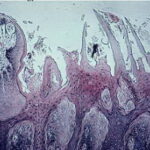

Section of surface of tongue = مقطع في سطح اللسان